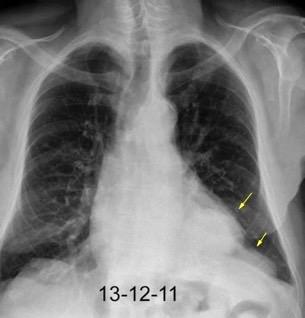

Síndrome de afectación postcardiaca (postcardiac injury)

Post infarto 1-7 % (Dressler)

Trauma cerrado Implantación marcapasos

Cirugía cardiaca. 17-31% (Post.pericardiotomía)

3707 pacientes 29 Derrames (0,78%) > de 25% del hemitórax

Todas menos 2 Izdos.

Angioplastia

By-pass coronario 21-10-03